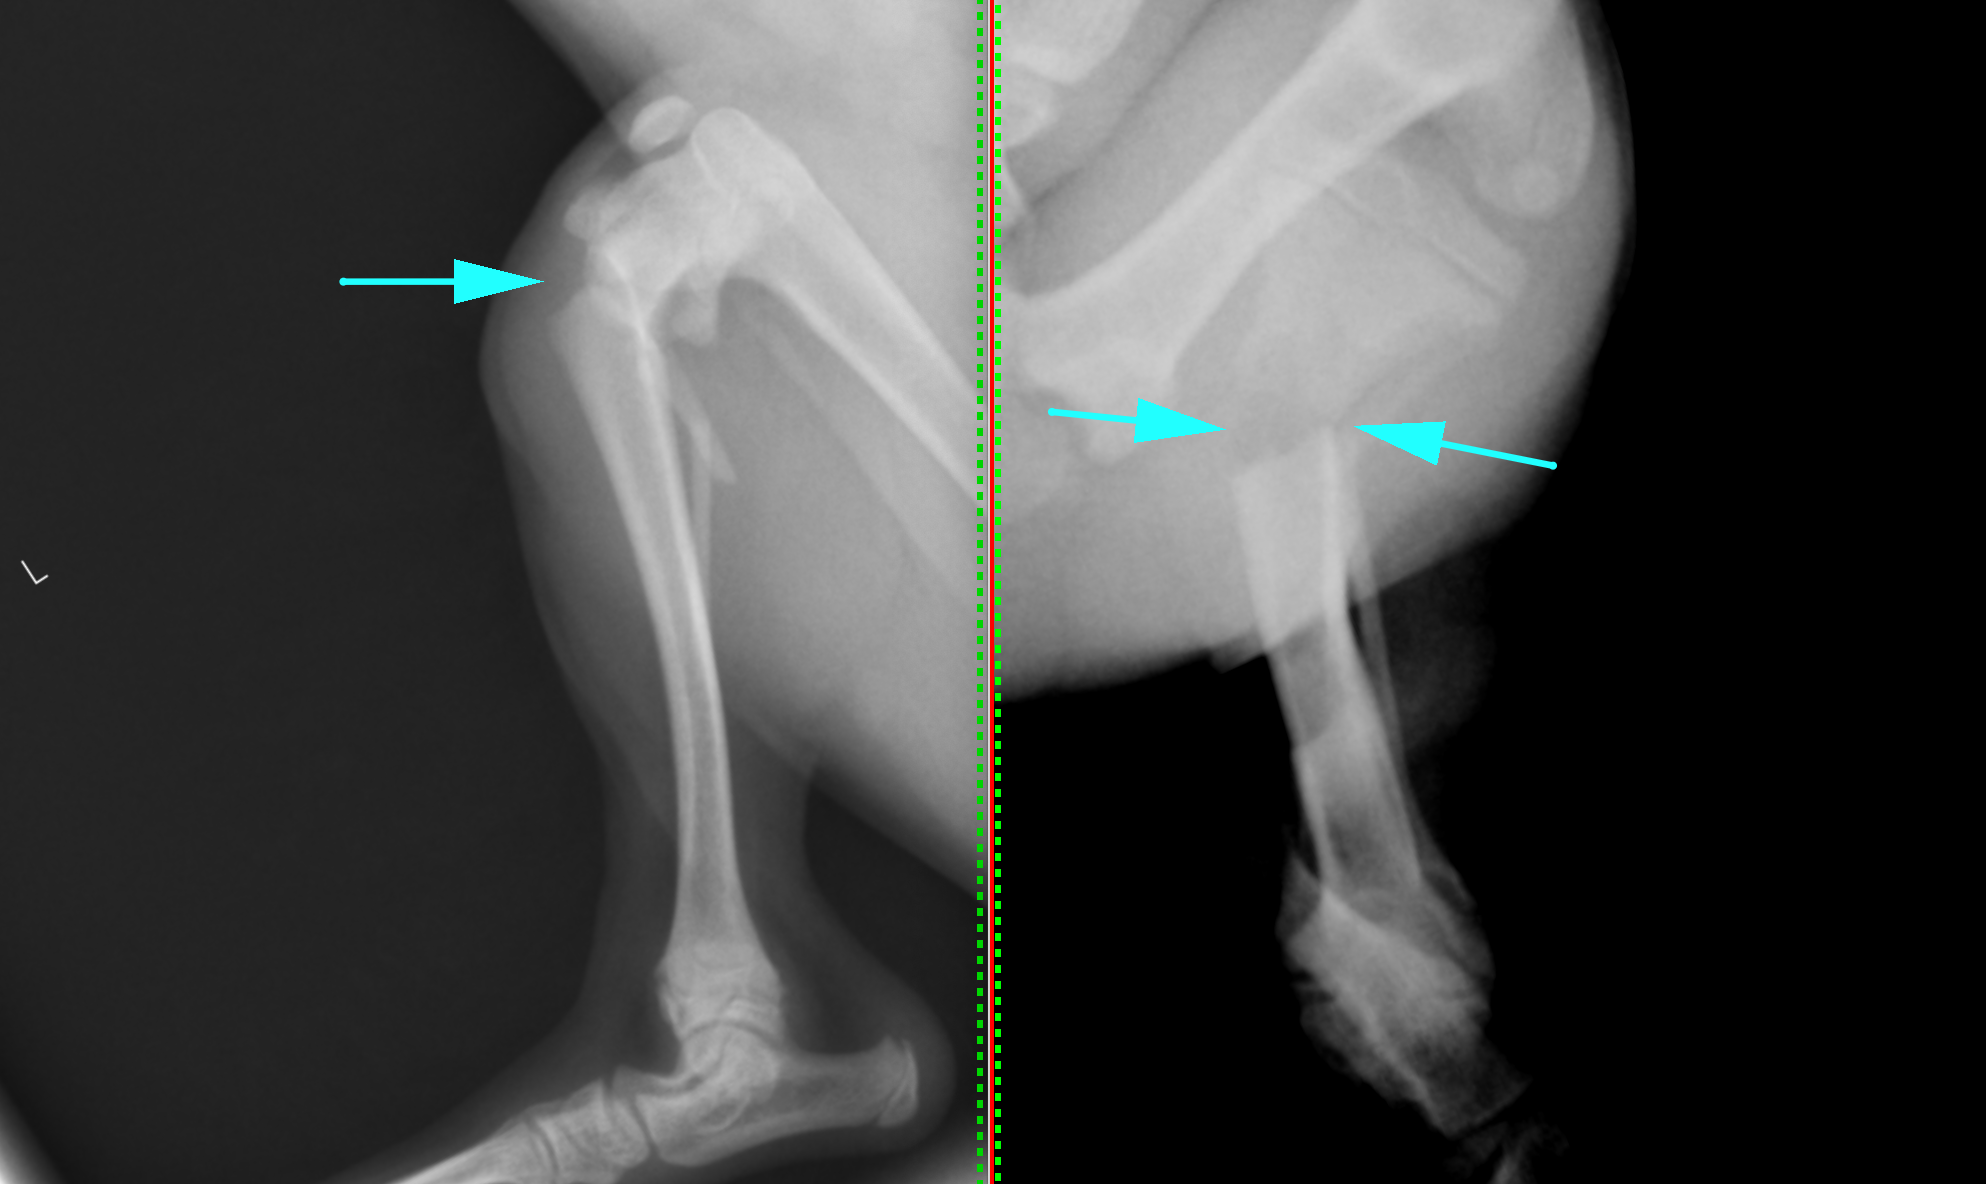

患者さんはトイ・プードルの4ヶ月齢、1.8kgでした。抱っこしていて落としてしまってから足を挙げるとのことで来院されました。X線で脛骨骨折が確認され、そのなかでも近位側が折れているのが分かりました。

矢印の部分で折れているのが分かります。

完全に折れてしまっているのが分かります。すぐに手術できたので、骨折面はきれいです。